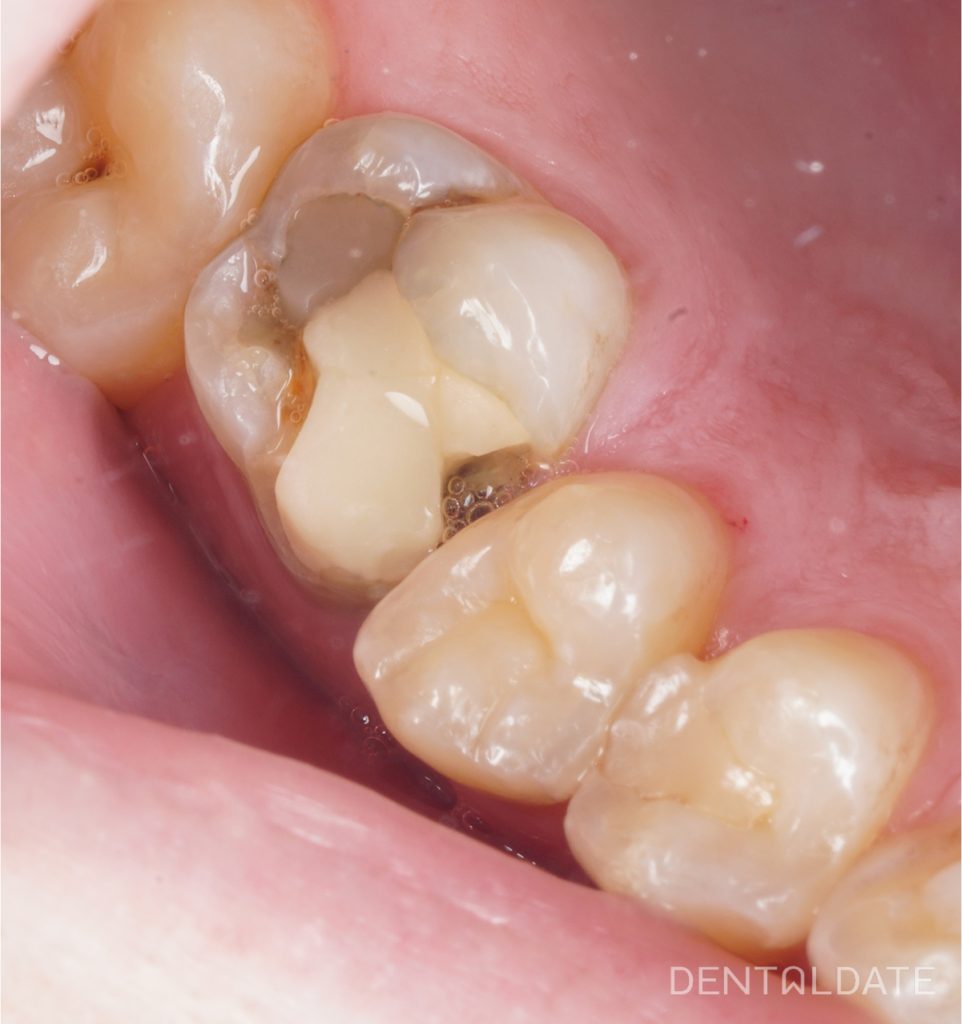

Пациент обратился в клинику с жалобой на разрушение верхнего зуба справа, застревание пищи.

Объективно: непригодная пломба на оклюзионной и медиальной контактной поверхностях зуба 1.6. Нарушено ее краевое прилегание, вторичный кариес. Перкуссия безболезненная.

Были сделаны КЛКТ и прицельные снимки, где выяснилось, что зуб был ранее лечен эндодонтически в другой клинике много лет назад. Пациенту было проведено эндодонтическое перелечивание зуба с последующей его реконструкцией под коронку, которое мы называем билдап.

В силу того, что зуб был первично лечен много лет назад. Стенки зубы разрушены на половину составляющей коронковой части зуба и они хрупкие, (теряя пульпу зуб теряет эластичность) такие зубы рекомендовано покрывать коронкой, дабы избежать их разрушения и потери. Но перед этим проводится их терапевтическое реконструирование – восстановление отсутствующих стенок из композитного материала – билдап. При разрушении более 50% коронковой части зуба билдап делается с использованием внутрикорневого штифта.

В данном случае оставшихся тканей было достаточно. Чтобы сделать билдап без штифта.